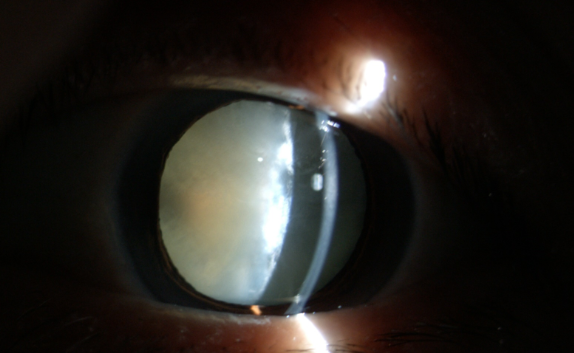

糖尿病為什么更易得白內(nèi)障

【文章導讀】在臨床中,很多糖尿病患者不太重視診治,尤其忽視糖尿病導致的多種眼科并發(fā)癥,如白內(nèi)障。糖尿病友得白內(nèi)障較普通人來說有三個特點:

在臨床中,很多糖尿病患者不太重視診治,尤其忽視糖尿病導致的多種眼科并發(fā)癥,如白內(nèi)障。糖尿病友得白內(nèi)障較普通人來說有三個特點:

(1)糖尿病患者比一般老年人白內(nèi)障發(fā)生率高;

(2)糖尿病患者比一般老年人白內(nèi)障發(fā)生早;

(3)糖尿病患者比一般老年人白內(nèi)障成熟快。

白內(nèi)障癥狀

糖尿病患者合并白內(nèi)障盡早手術(shù)的原因:白內(nèi)障發(fā)生后,不但使患者視力產(chǎn)生障礙甚至失明,還直接影響到醫(yī)生對眼底的檢查和治療,因為渾濁的晶狀體阻斷了進出光線。因此,糖友們的白內(nèi)障手術(shù)治療,既能解除視力障礙,還能掃除糖尿病視網(wǎng)膜病變的檢查、治療障礙,所以應盡早手術(shù)。